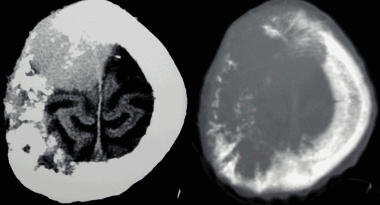

МРТ головного мозга. Сагиттальная и аксиальная Т1-взвешенные МРТ, аксиальная Т2-взвешенная МРТ и аксиальные КТ и Т1-взвешенная МРТ с контрастированием. Гигантоклеточная астроцитома с кальцификацией - внутрижелудочковая опухоль.

КТ и МРТ головного мозга. Аксиальные КТ до и после контрастировали, сагиттальная МРТ с контрастировавшем, аксиальная Т2-взвешенная МРТ головного мозга. Герминома (КТ и МРТ)- опухоль области шишковидной железы